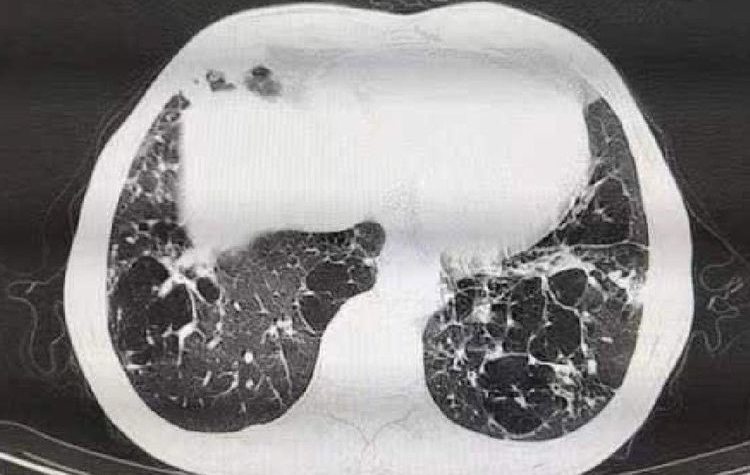

诊断意见:慢支,肺气肿,肺大泡;双肺下叶感染;纵隔内多发陈旧性淋巴结;甲状腺右侧叶低密度灶;肝右叶类圆形低密度灶。

该病例为老年患者,有五年高血压病史,咳嗽咳痰10年史,同时CT示肺气肿,肺大泡,双肺下叶感染。入院前抗感染治疗有所好转,7月17日患者咳嗽咳痰,加重伴有咯血,出现气促症状,临床考虑患者属于免疫功能低下,给予哌拉西林十莫西沙星联合抗感染经验治疗,同时送检痰液行一般细菌培养,检出流感嗜血杆菌。7.22送检肺泡灌洗液,镜下可见革兰阳性,直角分支状,线团样的菌丝体,弱抗酸阳性,培养48小时有表面有皱褶,呈下陷“咬琼脂”菌落生长,质谱仪鉴定为诺卡菌盖尔森基兴诺卡菌。同期肺泡灌洗液外送mNGS:诺卡菌属病原估测浓度>1.0E+6copies/ml。考虑患者免疫功能低下,经微生物室和药学部会诊,改为磺胺类药物口服抗感染,明显好转,于7.28号出院。病人出院后遵医嘱常期口服复方新诺明,十二月底到我院复查CT,CT结果提示肺部感染已完全恢复,病人情况良好。

肺诺卡菌病为机会性感染,患者多伴基础疾病。该患者有5年高血压病史,且咳嗽咳痰十余年,近期出现咳嗽咳痰加重并伴有咯血,影像学检查提示慢支,肺气肿,双肺下叶感染,实验室检查血沉和降钙素原轻度升高,都是诺卡菌感染的危险因素。患者肺泡灌洗液中发现大量线团样的菌丝体,结合患者病史与临床表现,以及影像学特征,可诊断为肺诺卡菌病。口服莫西沙星抗流感嗜血杆菌,口服复方新诺明治疗诺卡菌,患者病情好转出院,嘱口服复方新诺明定期复查,12月底到复查CT,提示肺部感染已完全恢复。